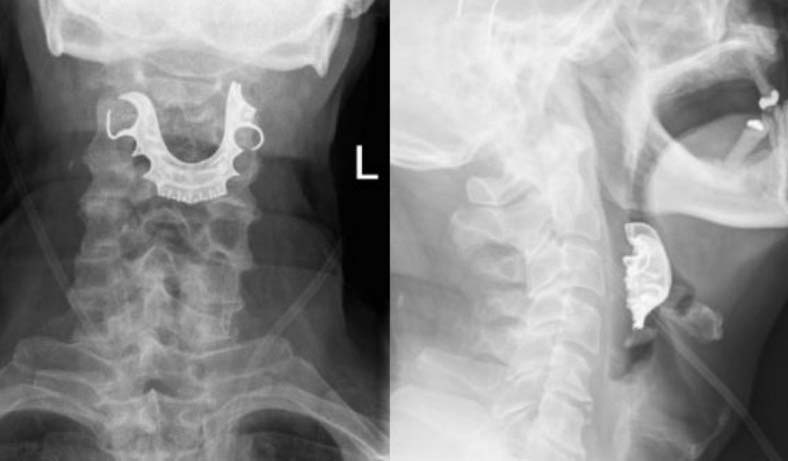

Os médicos pediram que o britânico fizesse uma radiografia do tórax, e o exame indicou que ele estava com uma pneumonia, então os especialistas receitaram antibióticos. O incômodo na garganta não melhorou e o idoso teve que voltar ao hospital.

Ele foi então submetido a novos exames e foi então a equipe médica identificou o problema: ele estava com suas próteses uma placa de metal e três dentes falsos armazenados no topo de sua garganta.